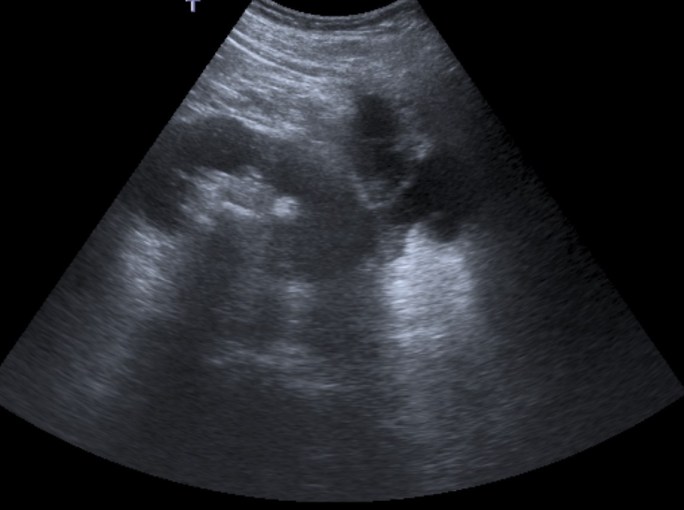

Ecografía:

- Agrandamiento y distorsión de la silueta renal.

- Pérdida difusa de la arquitectura renal normal.

- Gran ecogenicidad central amorfa que corresponde a un cálculo coraliforme en la pelvis renal.

Aunque estos hallazgos son más carácteristicos, se realiza posteriormente una TC para mejor valoración.

Paciente mujer de 62 años que acude por decaimiento general con fiebre y dolor en flanco izquierdo. Ingresa en UVI por signos de sepsis

Nos cuenta antecedentes de pielonefritis e hidronefrosis crónica.

Hallazgos en imagen:

Estos hallazgos pueden ser dificiles de interpretar, ya que una paciente con hidronefrosis crónica y litiasis en el uréter puede haber sufrido una obstrucción que origina un cuadro de dolor en FRI con ruptura de cálices y colección extra axial. Otra probabilidad puede ser un angiomiolipoma que ha roto un aneurisma y ha producido un sangrado. También podríamos estar ante una pionefrosis aunque dada dada la clínica, los antecedentes y al observar los hallazgos en TC podríamos establecer la sospecha de pielonefritis xantunogranulomatosa con alta probabilidad. La confrimación vendrá dada con la nefrostomía y estudio de anatomía patológica.